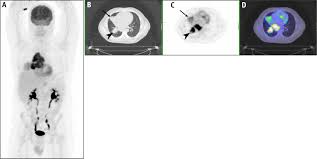

Whole Body Pet Ct For Initial Staging Of Choroidal Melanoma British Journal Of Ophthalmology

Whole Body Pet Ct For Initial Staging Of Choroidal Melanoma British Journal Of Ophthalmology from bjo.bmj.com